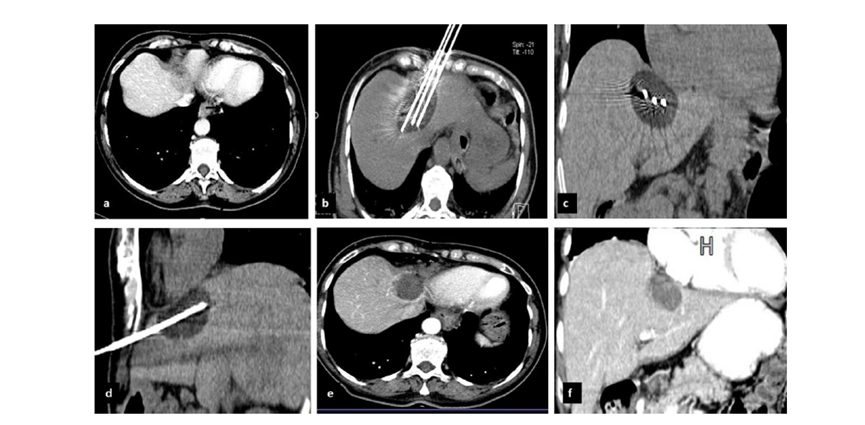

CT引導的冷凍消融